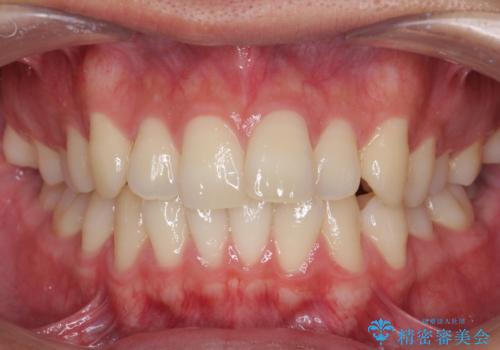

前歯を綺麗にしたい。

- 前歯を良くしたい(綺麗にしたい)との事で来院。

前歯のがたつきを治す治療プランとして

1 矯正を行い歯並びを良くする。(費用と時間がかかる)

2 セラミッククラウンで見た目を良くする(短時間で終わるが歯の向きを無理やり変えるために便宜的に歯の神経を抜く必要がある。健康な歯を削る)

のご提案をしたところ2のプランを選択されたのでセラミック治療を行いました。

見た目が良くなり大変満足して頂けました。